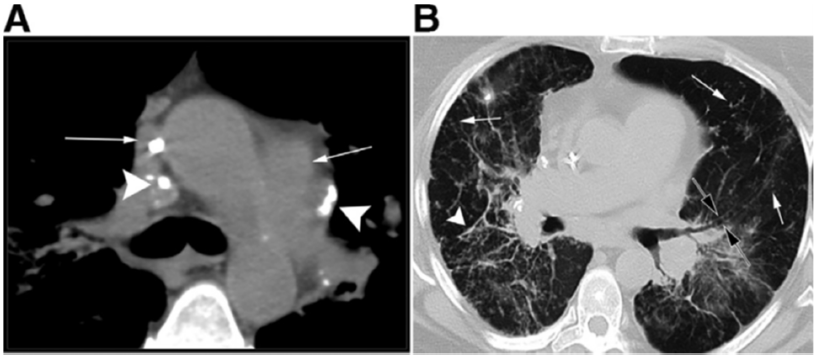

Tuttavia, la TC ad alta risoluzione (HRCT) è oggi considerata indispensabile per una migliore caratterizzazione. I segni tipici alla HRCT includono noduli a distribuzione perilinfatica (lungo i setti interlobulari e le scissure), ispessimento dei fasci broncovascolari e opacità a “vetro smerigliato” che riflettono un’alveolite granulomatosa attiva.